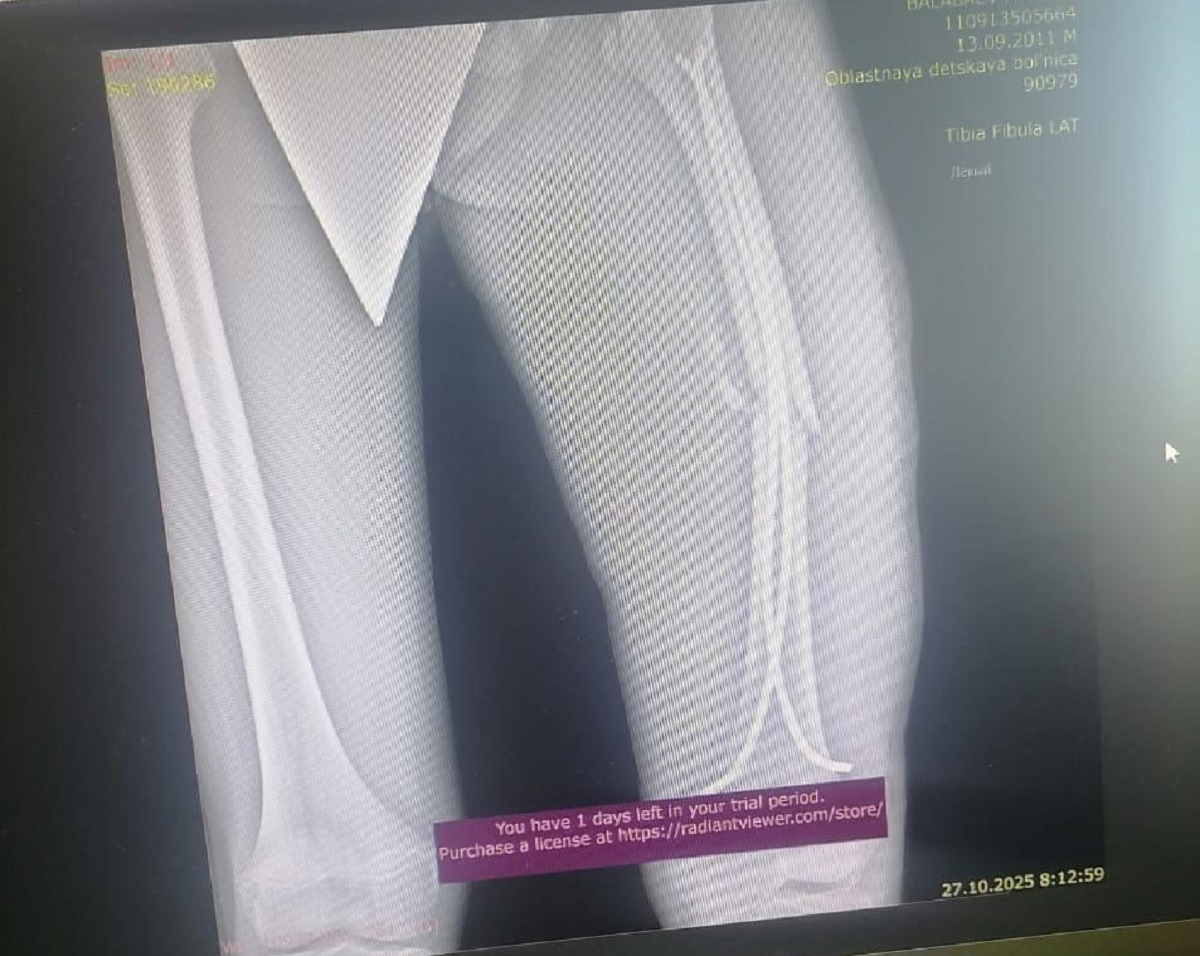

В результате падения подросток получил перелом бедренной кости со смещением и осколками средней степени тяжести. На место происшествия была вызвана скорая помощь, после чего Максима госпитализировали.

Сына экстренно прооперировали. Врачи говорят, что последствия могут быть серьёзными, нога может остаться деформированной или укороченной. По словам врачей, он может остаться инвалидом, хромать всю жизнь. Я подал заявление в полицию, чтобы потребовать компенсацию за ущерб здоровью. Там мне сообщили, что обращение направят в акимат, но до сих пор никакого ответа нет, - рассказал отец мальчика.